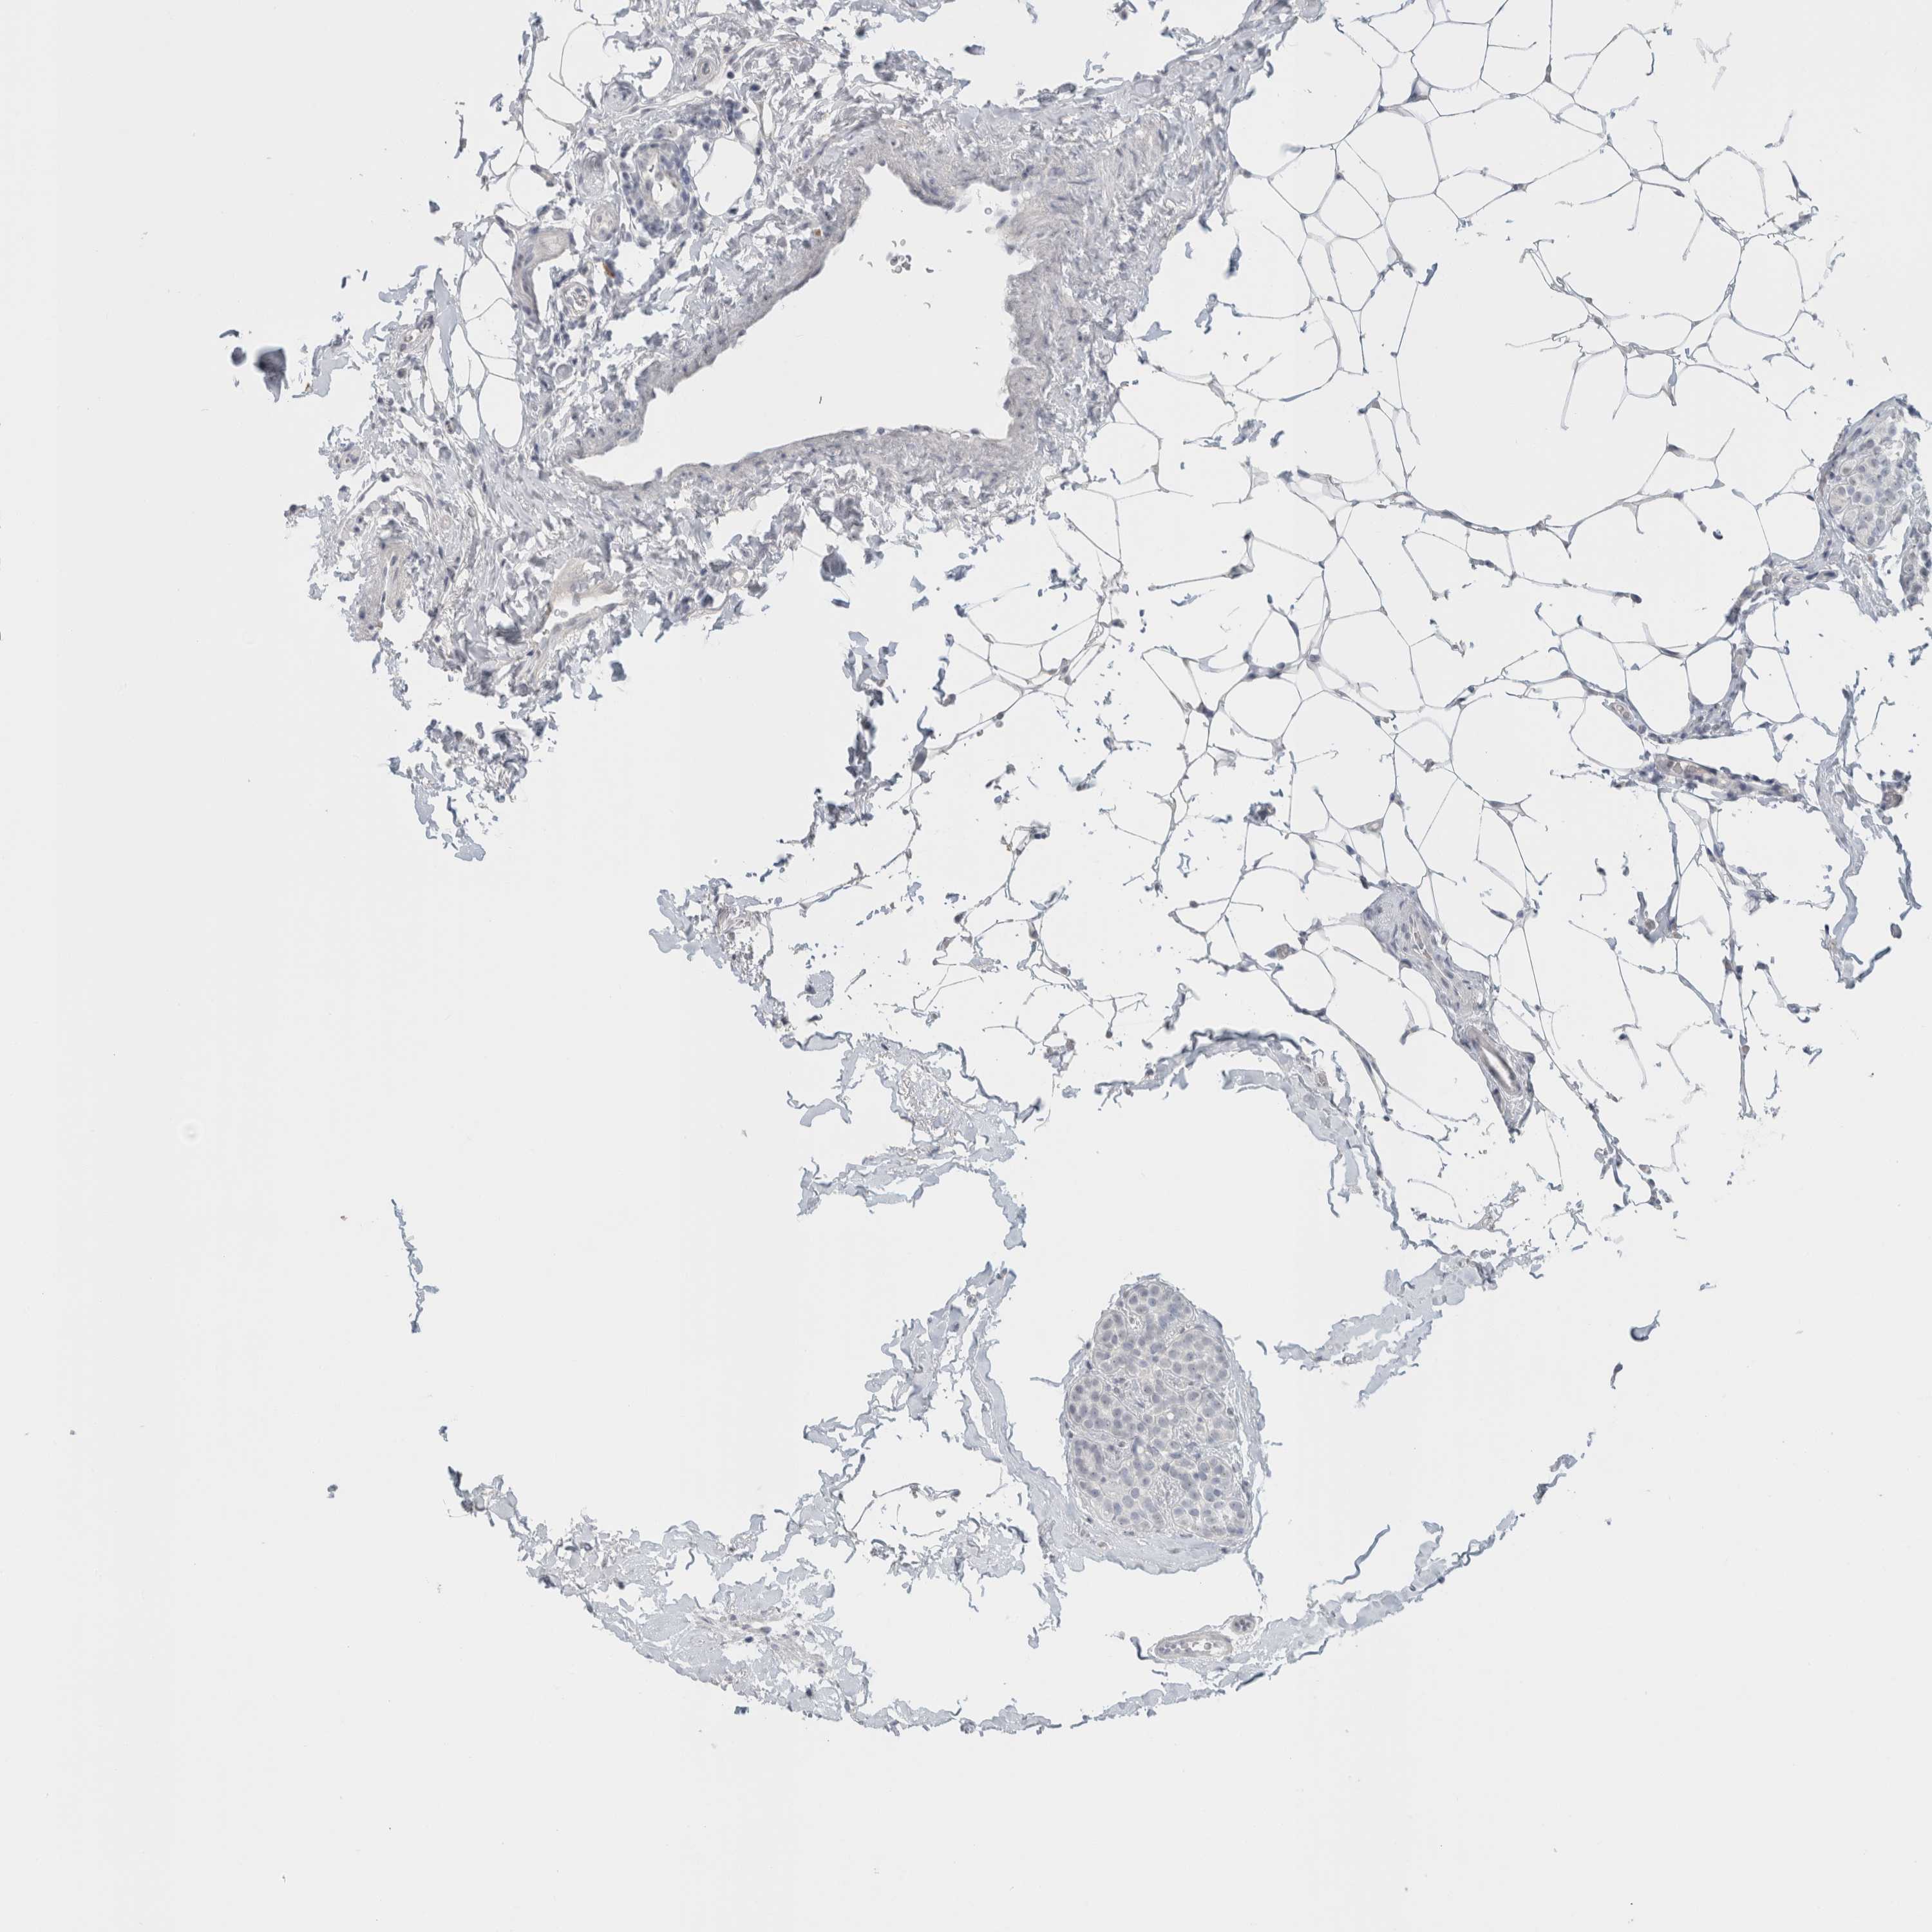

CANCER BREAST CANCER Show tissue menu

BRCA TCGA BRCA VALIDATION PROTEIN EXPRESSION